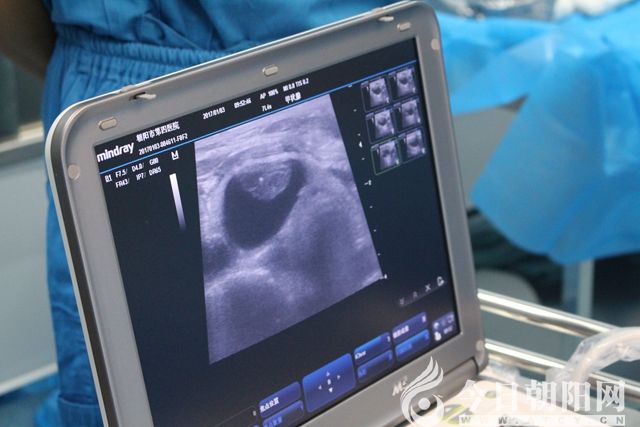

術前超聲定位

微波消融針穿刺至實性病變處,根據超聲引導,調整消融針,連續(xù)消融,至病變區(qū)域全部達到熱容效應?;颊咴谑中g中始終保持清醒,無明顯疼痛等不適感,偶有咽喉部輕度的腫脹感。術后4小時,患者離床活動,飲水無嗆咳,聲音無嘶啞。術后第3天,患者恢復良好,現(xiàn)已出院。